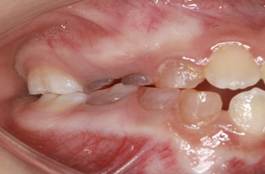

Figura 7. Relación molar derecha clase Figura

8. Relación molar izquierda clase III